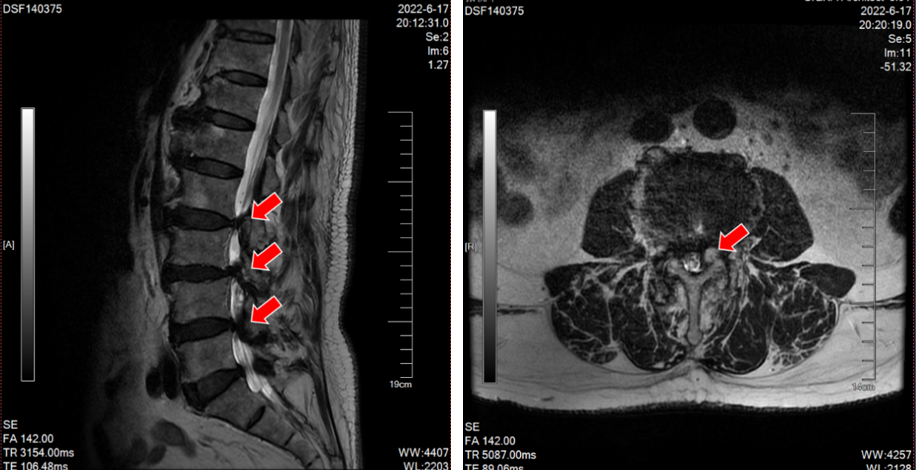

沈阿姨今年58岁,原本正是准备享受生活的年纪,但在今年5月,困扰了她长达4年的颈肩痛明显加重了。短短一周时间,沈阿姨的右上肢就出现了麻木感,吃药、理疗完全无法缓解,症状发展很快,于是立刻来我院骨科就诊。颈椎CT上可以清晰看到,她C4-5的椎间盘明显向右后方突出,椎间隙后缘骨赘增生,导致神经根受压。

(颈椎CT提示患者C5-6的椎间盘突出棒骨性狭窄)

(颈椎CT提示患者C4-5的椎间盘突出(右后方),椎间隙后缘骨赘增生)

在沈阿姨术后第三天,其表姐王阿姨也在她的推荐下来住院了。王阿姨的症状和沈阿姨几乎一样,在住院的前1个月,她右上肢的疼痛感突然加剧,病变的节段是C5-6,看到表妹的手术效果如此显著,她决定也来做手术。